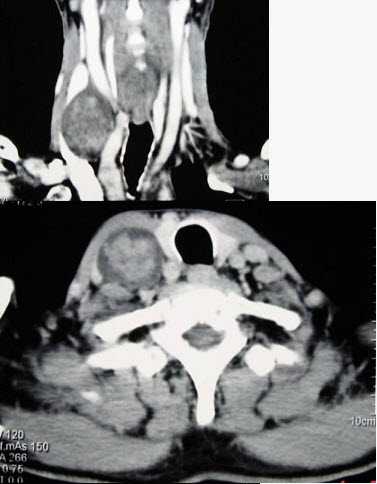

- 多项选择题男性,70岁,右侧颈部无痛性肿块3个月,CT扫描如图所示,请选择正确的描述和答案()。

A、右颈动脉间隙内见类圆形软组织肿块影,密度欠均匀,边缘光整

B、右侧颈静脉被推压至肿块外后方

C、右侧颈动脉被推压至肿块内后方

D、考虑迷走神经源性肿瘤

E、考虑交感神经源性肿瘤

- A,C,D